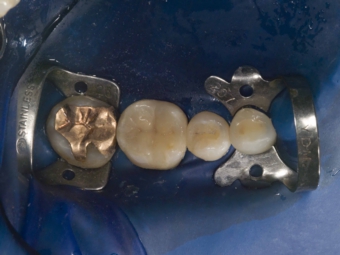

ラバーダム防湿

歯にラバー(ゴムの一種)で出来たマスクのようなものを装着し、唾液等による汚染から隔離します

マイクロスコープ

根管治療にはマイクロスコープは必須です

狭くて暗い根管の中を適切に清掃し、感染の除去を行う場合、20倍以上に拡大して観察が出来、診ている術者の視線の軸と光の軸が一致し、完全に見えるのがマイクロスコープです。

当院ではマイクロスコープを用いた精密な根管治療を行っております。